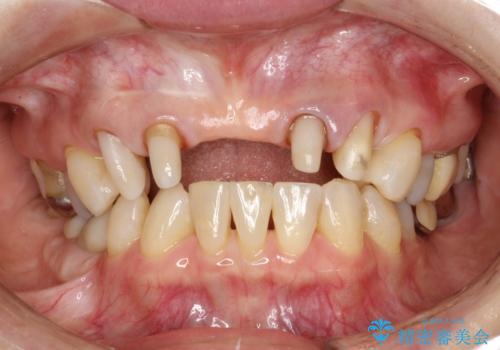

前歯のブリッジの見栄えが悪い→見えないところからしっかりとやり直しを

一見きれいにはいっているセラミックも、はずして中の状態をみるとひどいことが多い。これは、中の土台の状態や処理のクオリティは、短期的には問題を起こしづらく、患者さんには見えない部分だからです。